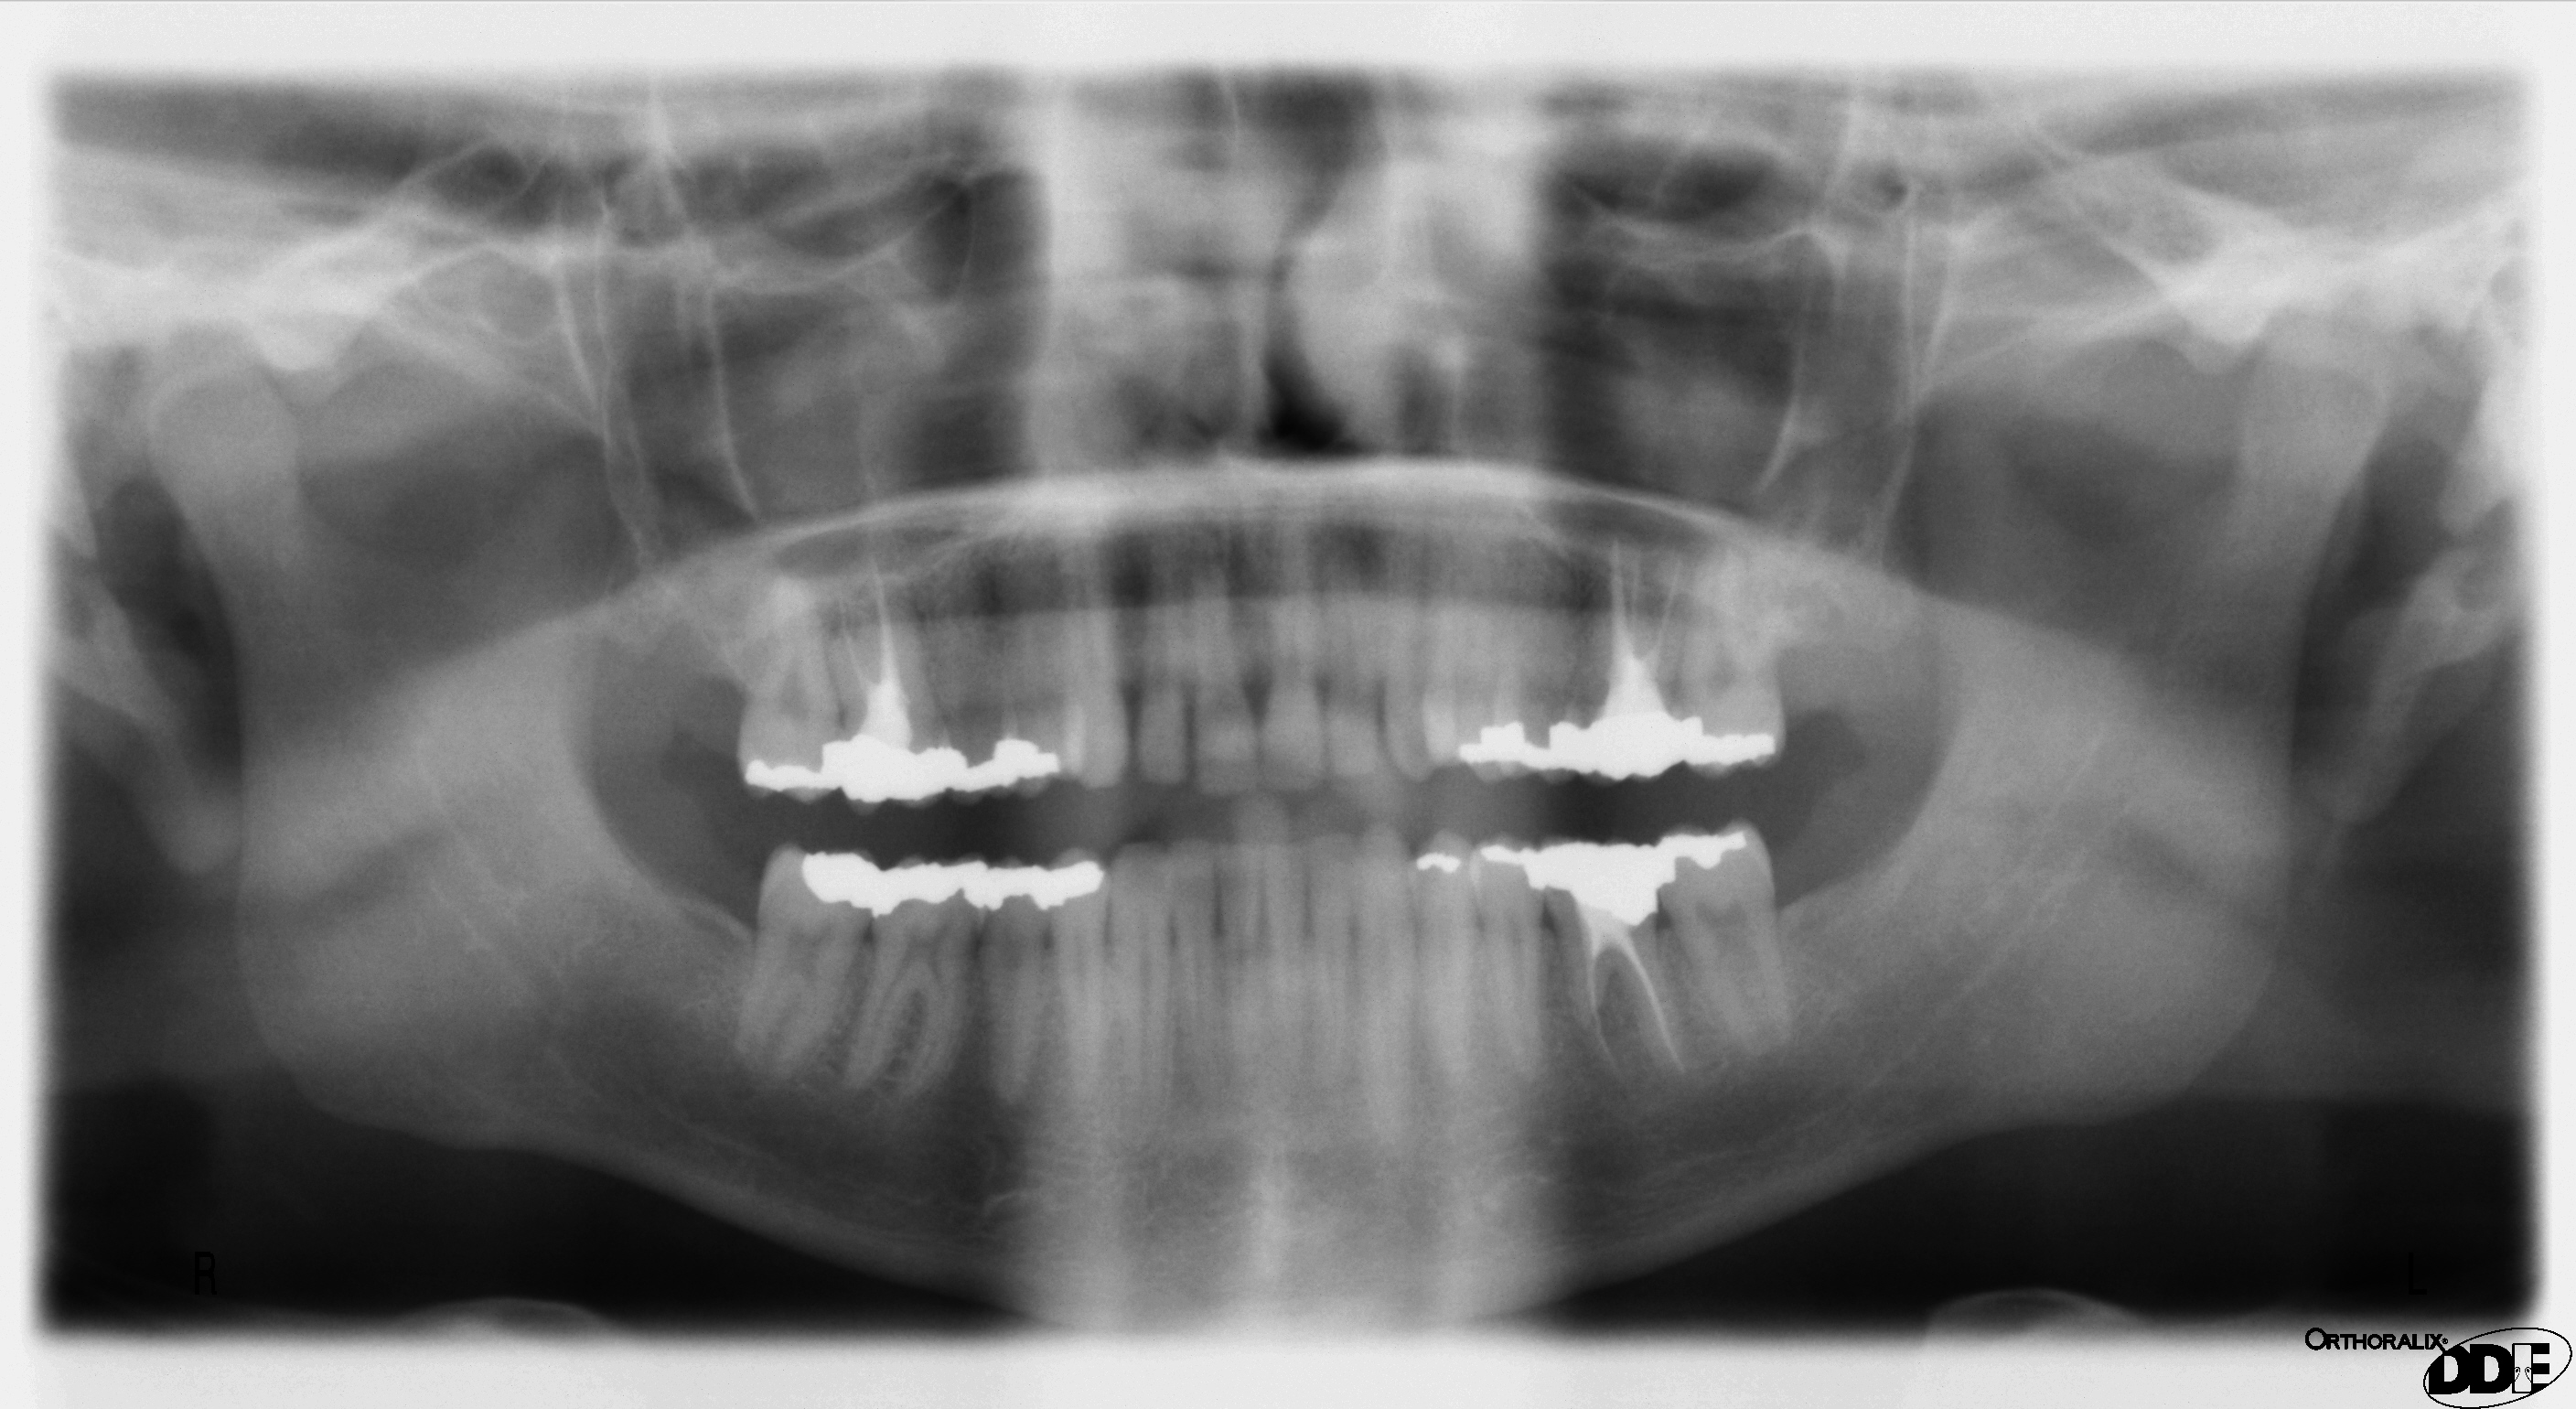

Pantomogram jako przykład obrazowania stomatologicznego

Pantomogram jest świetną mapą startową, ale nie zastępuje zdjęć punktowych ani CBCT, gdy pytanie wymaga większej precyzji.

OPG daje przegląd szczęki, żuchwy, zębów i części struktur sąsiednich. Pomaga zaplanować dalsze kroki, ale ma ograniczenia geometrii i ostrości.

Pantomografia

Przegląd szczęki i żuchwy: zęby zatrzymane, ósemki, zmiany kostne, stan ogólny uzębienia i planowanie dalszej diagnostyki.

W OPG znaczenie mają linia frankfurcka, pozycja języka, stabilizacja głowy i usunięcie metalu.

Pantomogram ma cienie duchy

Metal może tworzyć odbicia po przeciwnej stronie obrazu. Dlatego usunięcie biżuterii nie jest formalnością.

Język zmienia obraz

Brak kontaktu języka z podniebieniem tworzy ciemny pas powietrza nad korzeniami górnych zębów.